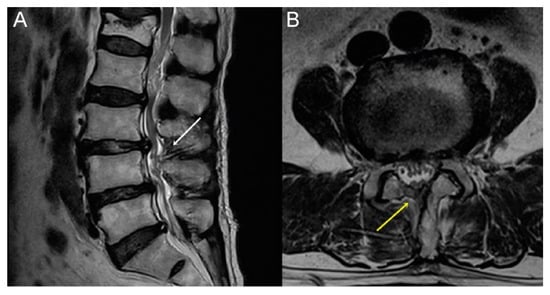

| MRI grading | 0.34 ¶ | |||

| A (Minor) | 50 (30.3) | 28 (16.97) | 22 (13.33) | |

| B (Moderate) | 58 (35.15) | 31 (18.79) | 27 (16.36) | |

| C (Severe) | 48 (29.09) | 27 (16.36) | 21 (12.73) | |

| D (Extreme) | 9 (5.45) | 6 (3.64) | 3 (1.82) | |